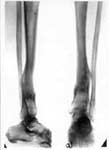

3.Результат лечения